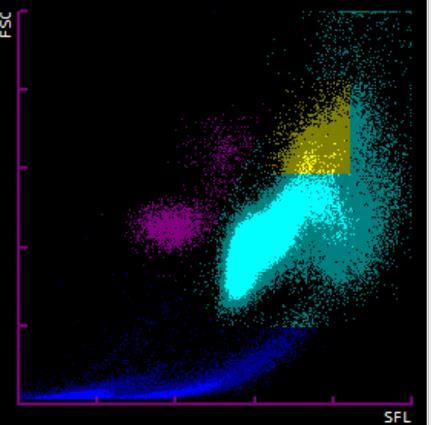

El aumento de los granulocitos inmaduros en la sangre periférica (mielemia) suele indicar una respuesta en su fase inicial de una infección, una inflamación u otros estímulos a nivel de la médula ósea. Este parámetro permite una discriminación rápida y temprana entre infecciones bacterianas y víricas, un apoyo al uso de otros parámetros inflamatorios como la PCR o las interleucinas y la monitorización de los pacientes infectados. Existen varias situaciones en las que el uso de medicamentos incrementa esta población. El más conocido es el uso de Factor Estimulante de Colonias de Granulocitos (G-CSF), utilizado en pacientes oncológicos para la recuperación del sistema inmune. Un caso menos conocido es el uso de corticoterapia. En el siguiente caso (Figura 4a) se observa la gráfica de una mujer de 41 años en seguimiento por endocrinología en la que se observa trombocitosis (571 x 103 plaquetas/uL), leucocitosis (21,99 x 103 leucocitos/uL), neutrofilia absoluta (16,67 x 103 células/uL) y discreta monocitosis (1,23 x 103 células/uL). Se observa una población de granulocitos inmaduros de 1,86 x 103 células/uL, lo que se observa como una población de alta fluorescencia por encima de la población de neutrófilos. La mielemia se confirma mediante revisión del frotis de sangre periférica donde se observa así mismo una intensa granulación. Revisada la historia clínica y teniendo en cuenta que los marcadores inflamatorios son negativos, se sugiere revisar las causas farmacológicas, como el uso de corticoides, que pueden explicar esta población anormal. Otra situación en la que aumentaría esta población es la leucemia mieloide crónica. El siguiente caso (Figura 4b) corresponde a un varón de 24 años sin antecedentes de interés. En el análisis hematimétrico se observa una leucocitosis muy marcada (155,89 x 103 leucocitos/uL) principalmente debida al aumento de neutrófilos (130,75 x 103 células/uL), dentro de los cuales 48,38 x 103 células/uL (37 % de la población de neutrófilos) corresponden a granulocitos inmaduros. Además, se observa trombocitosis (775 x 103 plaquetas/uL), basofilia (10,23 x 103 células/uL, un 6,5 % del total de leucocitos) y presencia de 14 eritroblastos por cada 100 leucocitos. La fórmula se confirma por microscopía digital.

Figura 4. a) Presencia de mielemia. Se señala la población de granulocitos inmaduros. b) Leucemia Mieloide Crónica (LMC). Se señala la población de basófilos. Elaboración propia